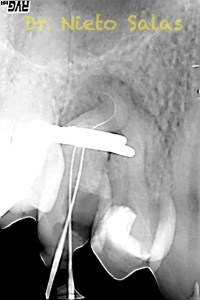

Se nos presenta en la clínica un par de casos de características similares, con lo cual las hemos tratado igual:

Ante estas situaciones, lo que no debemos es intentar llegar a la zona apical rápido, primero prepararemos el tercio medio-coronal, pero sin perder la permeabilidad del conducto con limas de muy pequeños diámetro.

Una vez que tenemos la Long de trabajo, no debemos perderla, se recomienda mucha irrigación e intentaremos que nuestras limas trabajen en una superficie lo menor posible.

La obturación la haremos con el sistema de condensación vertical por ola continua de Buchanan.

Conseguiríamos un sellado de esta manera en el caso A:

Y  de forma muy similar en el caso B; en este caso el paciente vino a la revisión a los 9 meses evidenciado el éxito en el tratamiento:

Con respecto a lo puramente endodóntico, la verdad que fueron unos casos de verdadero estrés para no perder la permeabilidad ni la long de trabajo, con técnica corona-apice y con un diametro apical de 20, instrumentado solo la parte apical con limas de Mtwo , la parte coronal me ayudé de ultrasonidos. No sé, que más contarte con respecto a la conformación de los conductos.

La verdad, no me planteé la posibilidad de la obturación con Thermafil, se trataba de un caso con un sistema de conductos con un itsmo coronal, y pienso que la obturación con sistema de ola continua me garantizaba un mejor sellado.